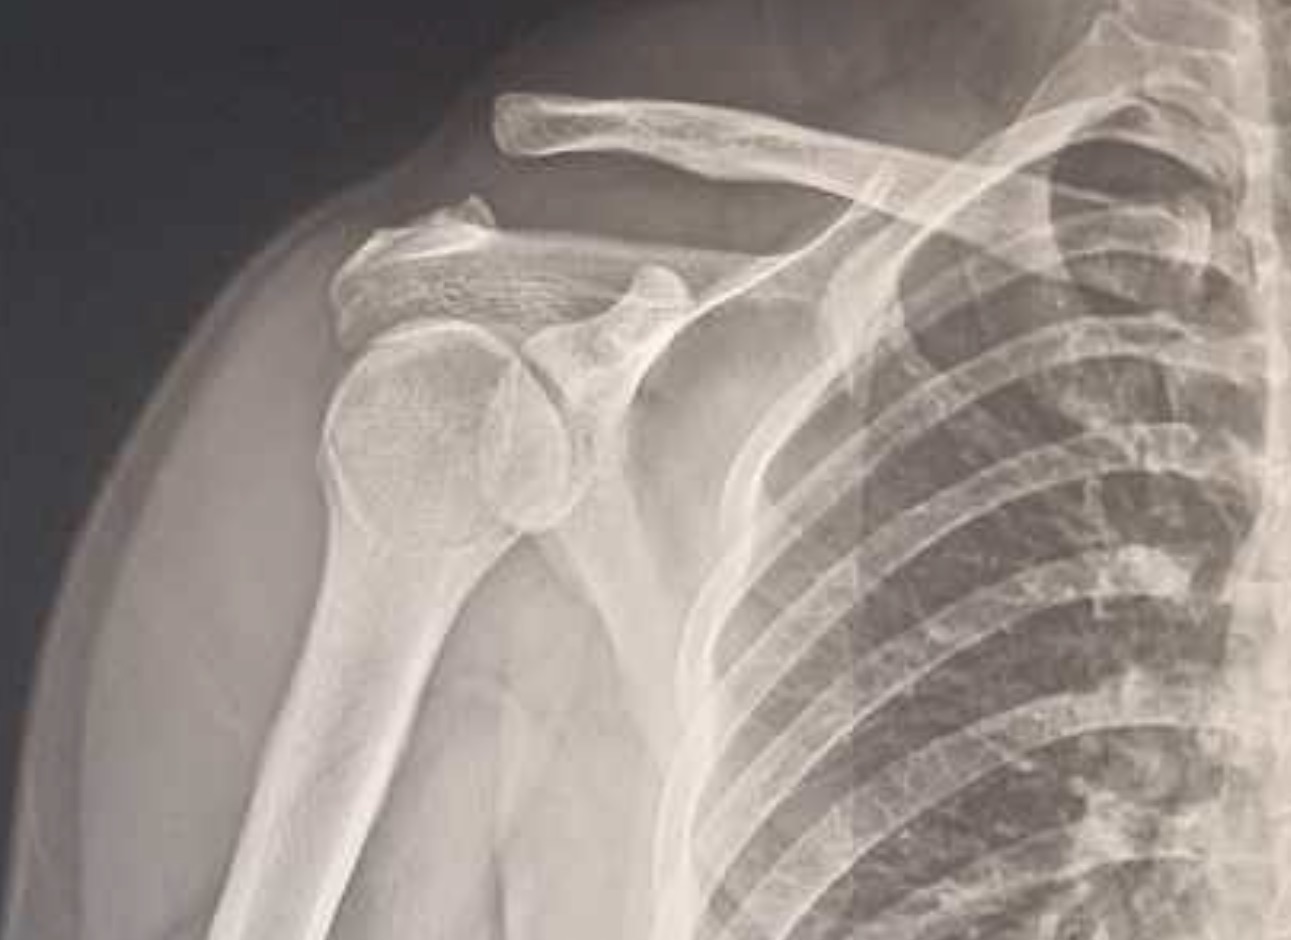

การตรวจวินิจฉัย: มากกว่าแค่การเอกซเรย์

หลายคนสงสัยว่า "ทำไมเอกซเรย์แล้วหมอบอกปกติ แต่ยังปวดอยู่?"

คำตอบคือ เอกซเรย์ (X-ray) จะเห็นแค่ "กระดูก" ครับ มันช่วยบอกได้ว่ากระดูกงอกไหม ข้อเสื่อมไหม หรือกระดูกผิดรูปหรือไม่ แต่เอกซเรย์ "ไม่เห็นเส้นเอ็น" ครับ ดังนั้นถ้าเส้นเอ็นขาด แต่กระดูกยังดี ผลเอกซเรย์ก็จะดูเหมือนปกติ